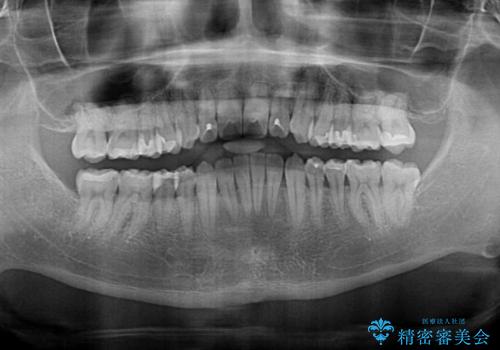

オープンバイトと目立つ銀歯 インビザライン矯正とセラミック修復治療

- 奥歯の目立つ銀歯と上下前歯の叢生と隙間を気にして来院された患者様です。

開咬の治療は、前歯を閉じるように動かすとともに、上下臼歯を圧下(骨内にめり込ませる)させることで進めて行きます。

インビザラインは臼歯の圧下を効果的に行えるため、インビザラインを用いて矯正治療を行うこととしました。